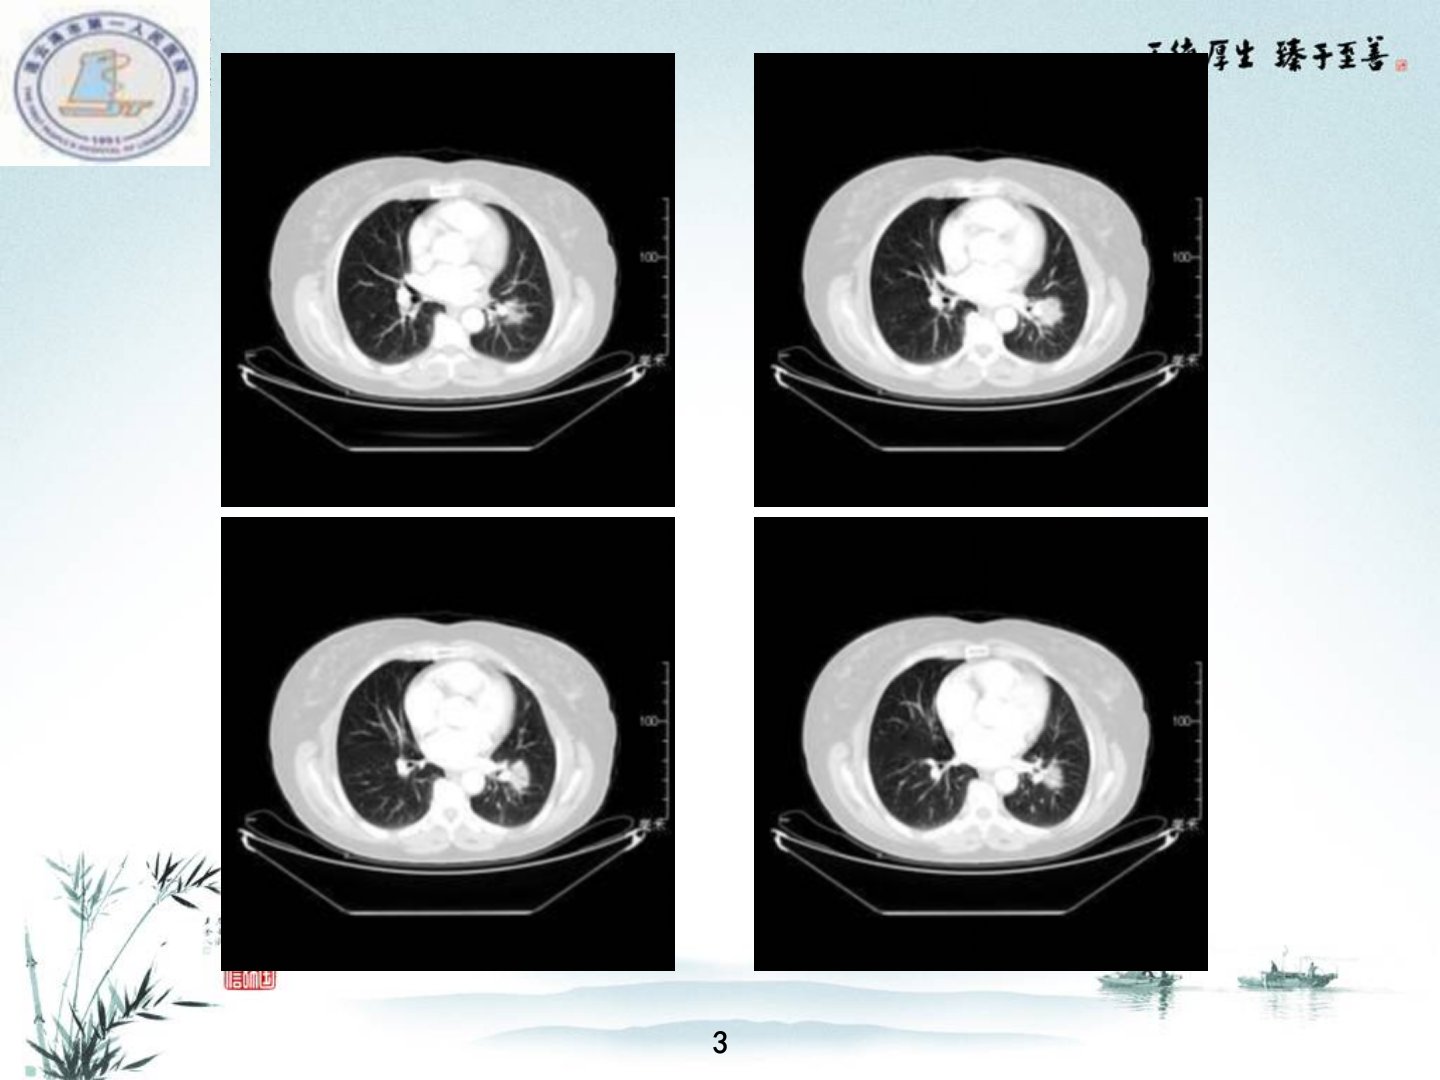

连云港市第一人民医院刘雨成分享了胸部少见病的诊断案例。病例1为60岁女性诊断为左肺下叶粘膜相关性B细胞淋巴瘤发病率低多见于中老年起病隐匿CT表现为肺内团块状或大片状阴影。病例2为83岁男性诊断为炎性肌纤维母细胞瘤真性肿瘤有复发潜能多见于40岁以上中年人CT表现多样多呈肿块影。病例3为69岁男性诊断为肺部孤立性纤维瘤非常罕见多为良性影像表现为有完整包膜的孤立性肿块确诊需病理及免疫组织化学。病例4为86岁男性诊断为纵隔高分化血管肉瘤罕见病因不清影像学表现多样最终诊断依靠病理。病例5为60岁男性诊断为恶性纤维组织细胞瘤极为罕见恶性度高预后差影像表现为周围型实质性肿物与胸膜及纵隔关系密切。